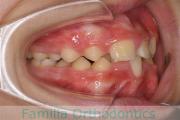

上の出っ歯、口が閉じにくい、下の前歯のガタガタを治したいということで来院されました。上顎から左右小臼歯を、下の前歯は凹凸が非常に強いので、こちらから一本抜歯を行いました。2年強、30回程度の通院が必要でした。

成人になってからの叢生(でこぼこ、凹凸、ガタガタ)は、保定をしっかりしないと後戻りをしてしまうリスクが高いです。

- ≫治療後

-

上顎

下顎

前歯の関係など

右側

正面

左側